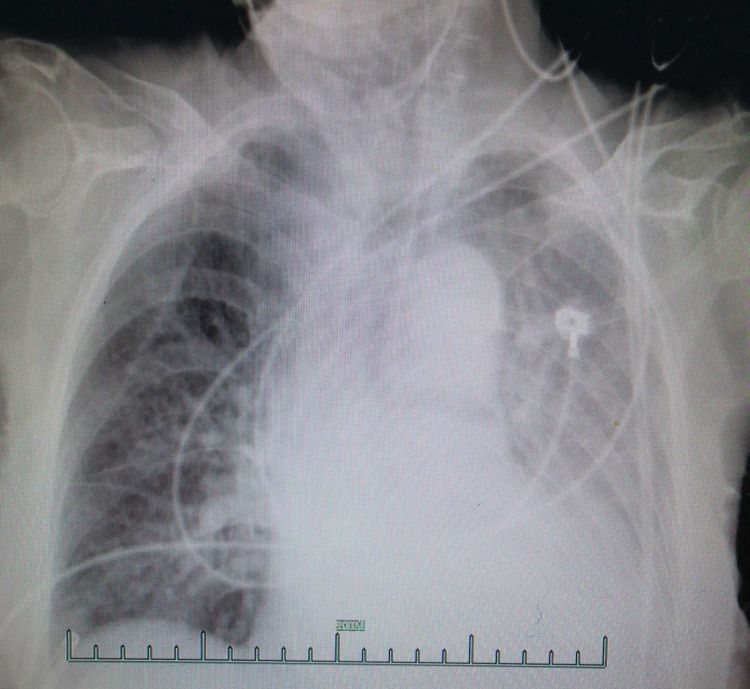

這是病人的CT和血?dú)猓苤?。家屬希望老人不要受太多痛苦,尊重患者家屬意愿,盡量減少有創(chuàng)操作。

經(jīng)過(guò)48小時(shí)的積極治療,患者乳酸開(kāi)始恢復(fù)正常,呼吸恢復(fù),血壓正常,復(fù)查胸片恢復(fù),尿量恢復(fù),各項(xiàng)指標(biāo)漂亮。

第二天復(fù)查的胸片